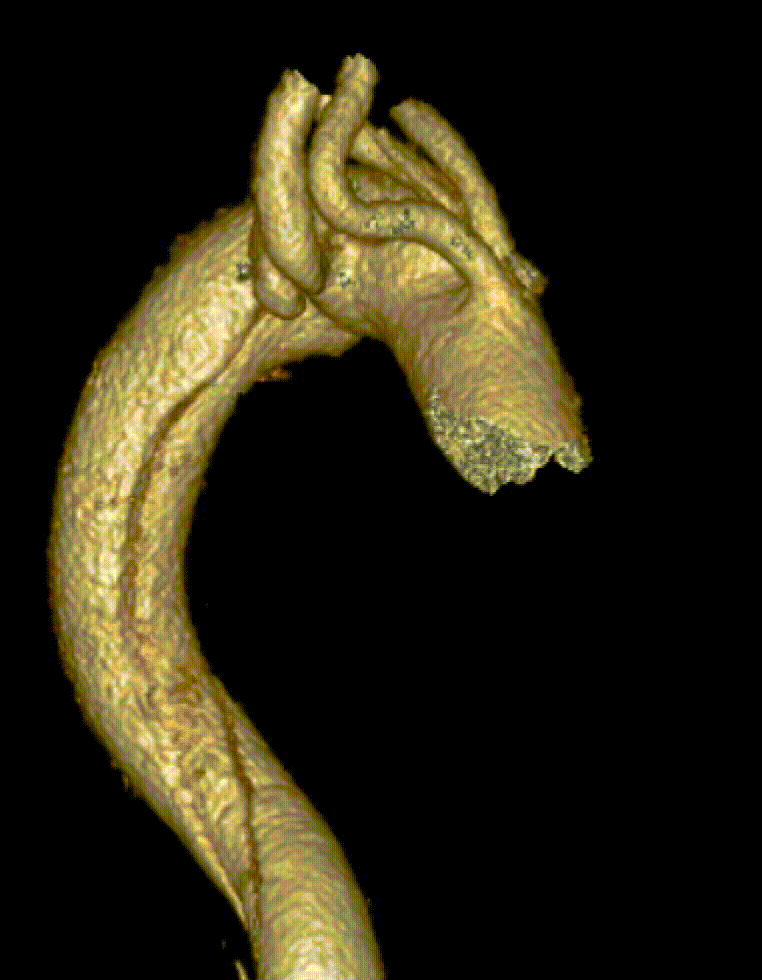

技术应用:这是一例夹层+迷走右锁骨下+单发左椎动脉+卡梅尔憩室的病例,通过TEVAR+LSA-LCCA转流+单发LVA-LCCA转流+迷走RSA-RCCA搭桥解决分支重建问题,远期效果良好。

AD+迷走RSA+单发LVA+KD